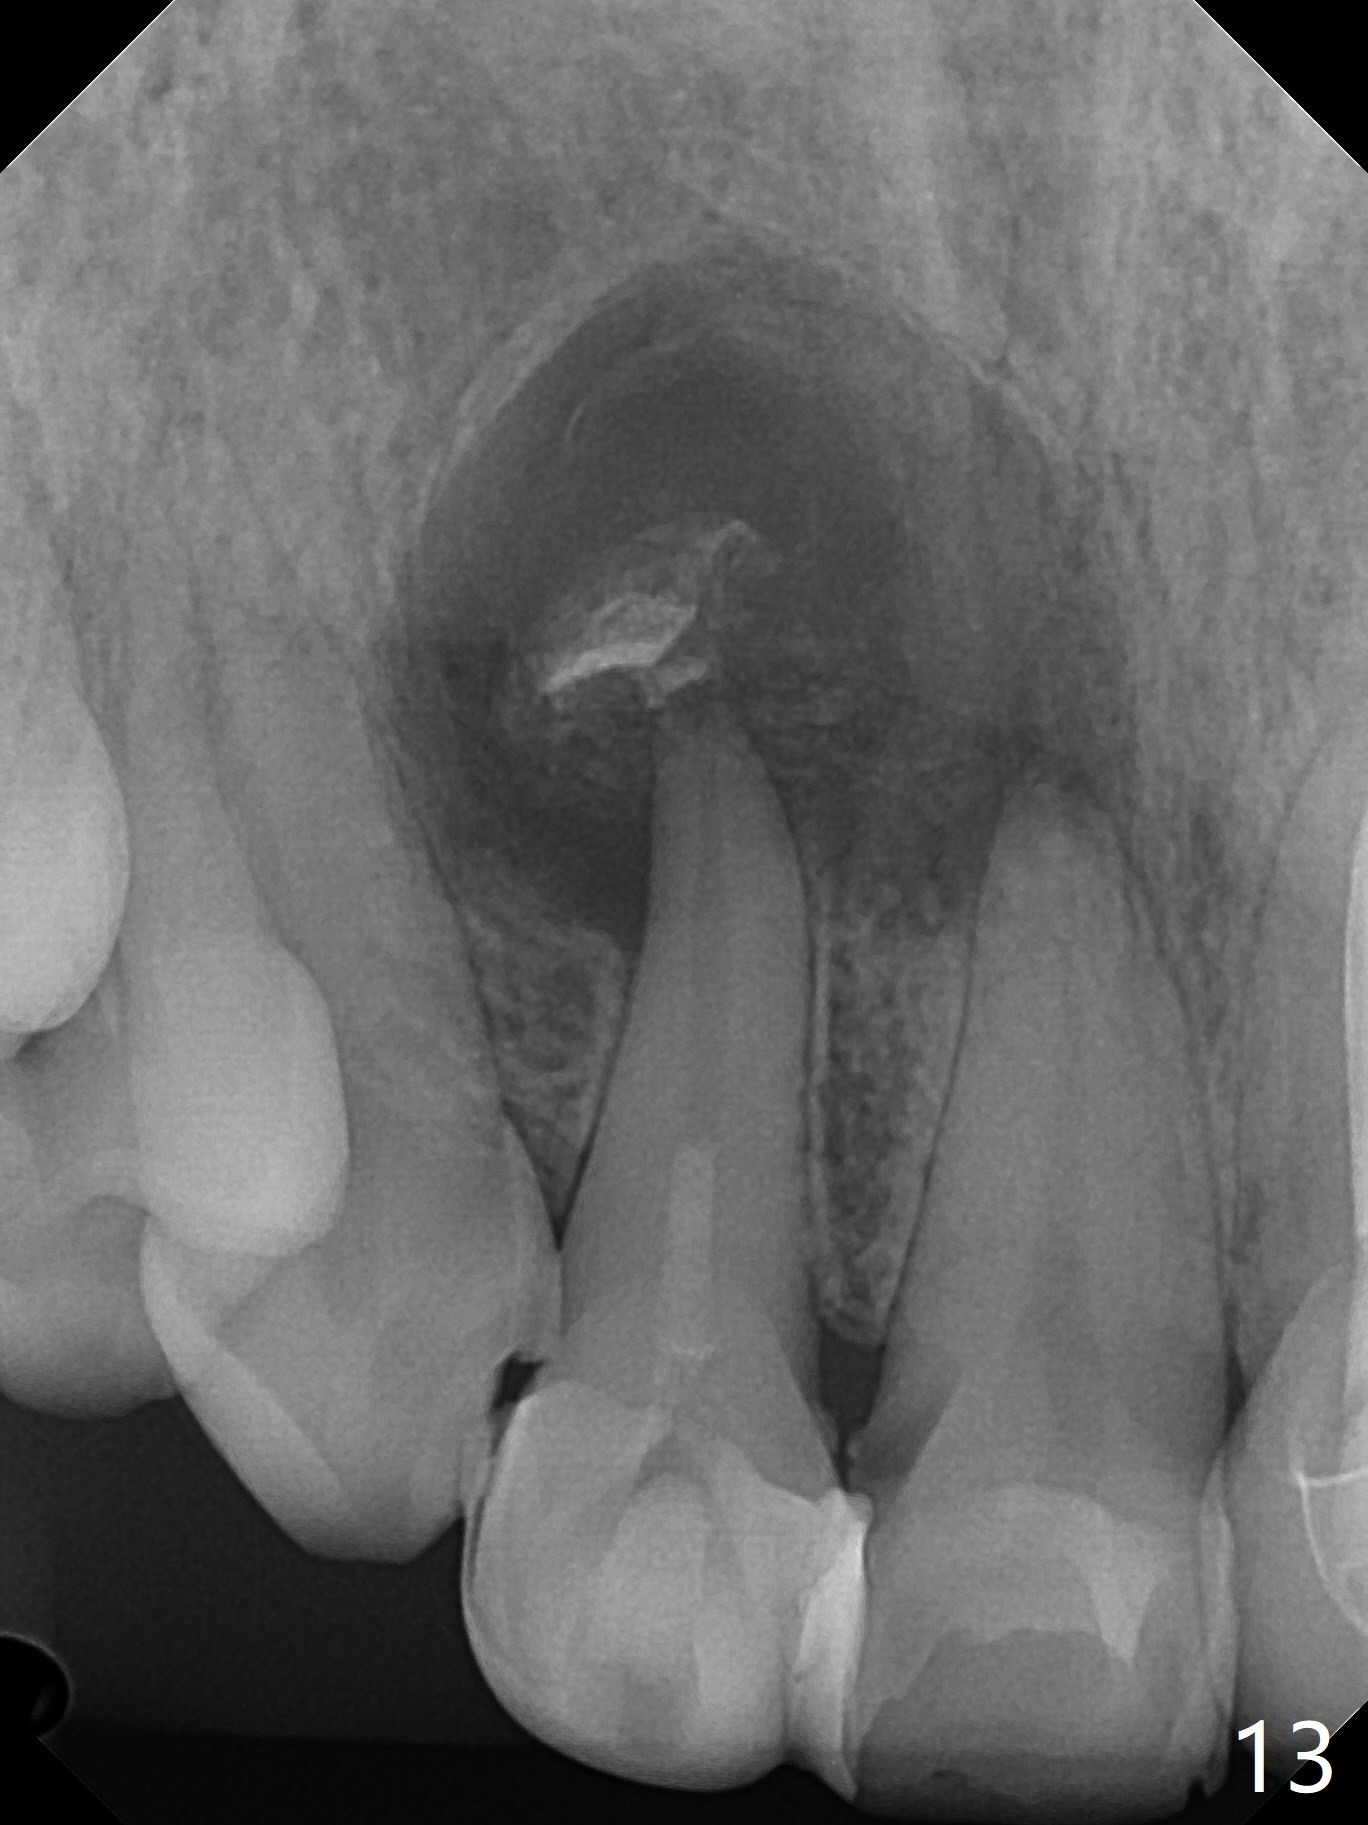

A 47-year-old woman (dental phobic) presented to clinic 9.5 years ago with periapical radiolucency (PARL) at #7 and 9 (Fig.1). RCT was done at #9 because of fistula and symptom 6 months later (Fig.2). While PARL increases at #7 without symptom, that at #9 disappears 8.5 years postop. Three months later, the patient returns for #7 RCT because of the abscesses (Fig.4 *) and pain. Intraop PA is taken with a 30/.06 rotary file in the canal with 19 mm working length (Fig.5). After use of #15 hand file for 20 mm, Ca(OH)2 paste is applied in the canal. When the rubber dam is removed, the abscesses enlarge (Fig.6), which may be related to sodium hypochlorite leakage. A dental explorer is used to try to find a bony opening to the large PARL without success (Fig.7). A postop PA reveals the leakage of Ca(OH)2 paste (Fig.8). Review of the preop PA (Fig.3,9) and intraop PAs (Fig.5,10) shows possible apical resorption and open apical foramen, which is the basis for the paste leakage (Fig.8,11). Careful analysis (with magnification and room light off) of pre- and intra-op PAs should be able to avoid use of #15 hand file out of apical constriction and the complication. The abscess has receded 1 month later (Fig.12). The paste has been resorbed 1 month later (Fig.13). A 30/.06 Gutta Percha is inserted at 18.5 mm (Fig.14 vs. 30/.06 file at 19 mm, 15 file at 20 mm last visit). Fig.15 is the final PA after closure of the access with composite (Fig.15).